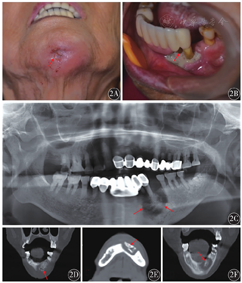

例2,女性,56岁,既往10年乳腺癌病史,出现骨转移3年,后续诊断出肝转移、脑膜转移。左侧胸骨上区和左胸壁接受放疗,全身接受紫杉醇+替莫唑胺化疗。使用唑来膦酸静脉滴注治疗24个月,后因肝损伤更换为伊班膦酸静脉给药,并遵医嘱用药10个月余。后因出现左上颌后牙区反复肿胀、疼痛、流脓停药。停药6个月后症状加重,来我院口腔科就诊。既往无糖尿病史,无拔牙史,无激素系统性治疗史,无颅颌面颈部放疗史。临床检查示:左侧面部明显肿胀,压痛(++),给予抗感染治疗后好转。开口度约2指半,左上颌前庭沟可查及黏膜瘘管,溢脓明显,探针可探及骨面,左上前磨牙、磨牙Ⅲ°松动。左上第二前磨牙、第一磨牙牙根对应牙槽骨暴露,暴露部位可见脓液渗出及伪膜形成(图3A、图3B)。全景X线摄片示:左上颌前磨牙、磨牙根尖不规则片状低密度影像,根尖骨质破坏吸收(图3C)。CBCT示:左上颌骨可见大块具有溶骨及硬化混合性表现的死骨形成,累及硬腭骨破坏,左侧上颌窦黏膜炎性增厚(图3D、图3E、图3F)。